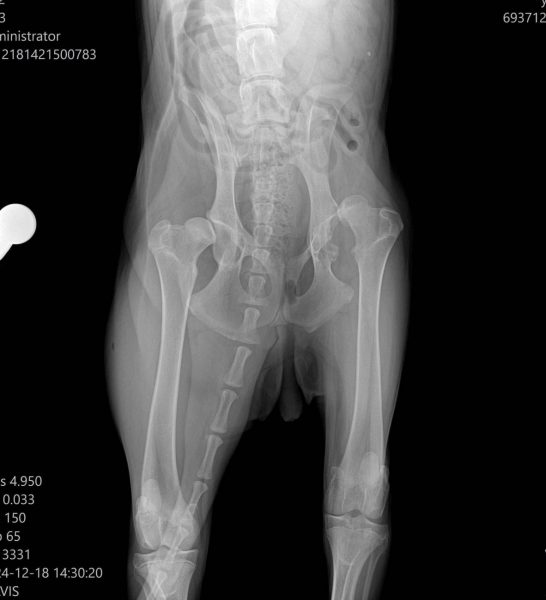

Ακτινογραφία σκύλου πριν από το χειρουργείο